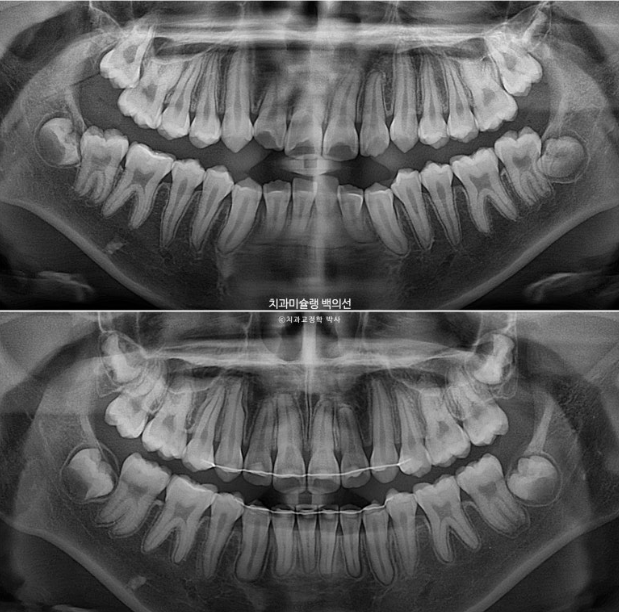

치료기간 내 치근흡수는 없고 치근평행도는 좋습니다.